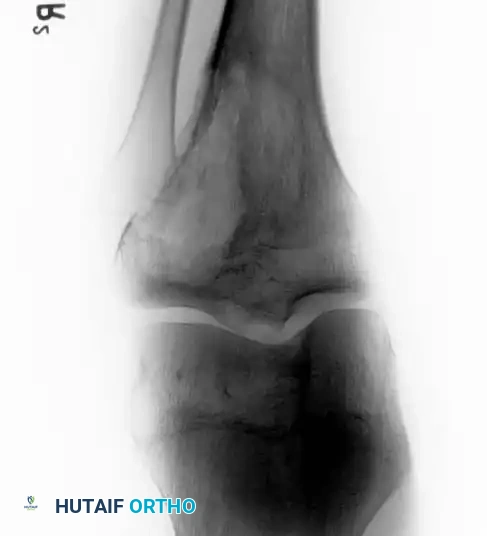

Intraoperative Imaging and Margin Assessment

Continuous intraoperative assessment using fluoroscopy and frozen section pathology is mandatory. The following images demonstrate various stages of complex upper extremity resections, allograft preparations, and prosthetic implantations across the humerus and elbow joint.

Distal Humerus and Elbow Reconstruction

When tumors involve the distal humerus, resection often requires sacrifice of the collateral ligaments and the articular surface of the elbow. Reconstruction is typically achieved using a linked, semi-constrained total elbow arthroplasty designed for oncologic defects.